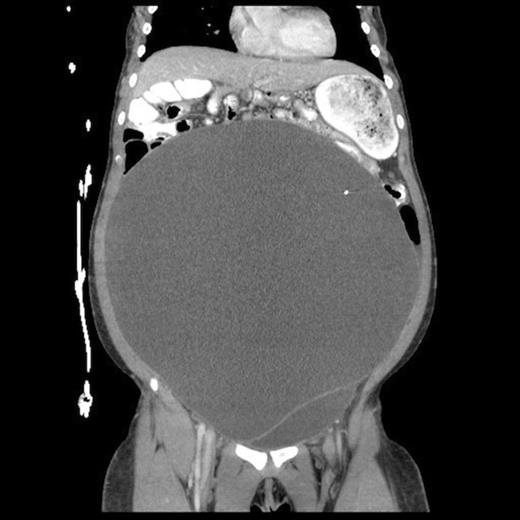

One-month follow up abdominal CT demonstrating recurrent formation of abdominal pseudocyst

The patient underwent laparoscopic cyst drainage with removal of the cyst wall. A total of 12.7L of fluid was drained. Culture results and routine labs were all negative. A post-operative CT demonstrated complete resolution of the fluid compartment (Fig. 4). The VP shunt catheter was initially left in the abdominal cavity. One month later, however, she developed significant recurrence of fluid collection (Fig. 5) and lethargy from malfunction of the VP shunt. The recurrent fluid was drained under ultrasound guidance, and her abdominal shunt catheter was removed. A new shunt catheter was placed in the right atrium, and the patient made a full recovery without any further complications.